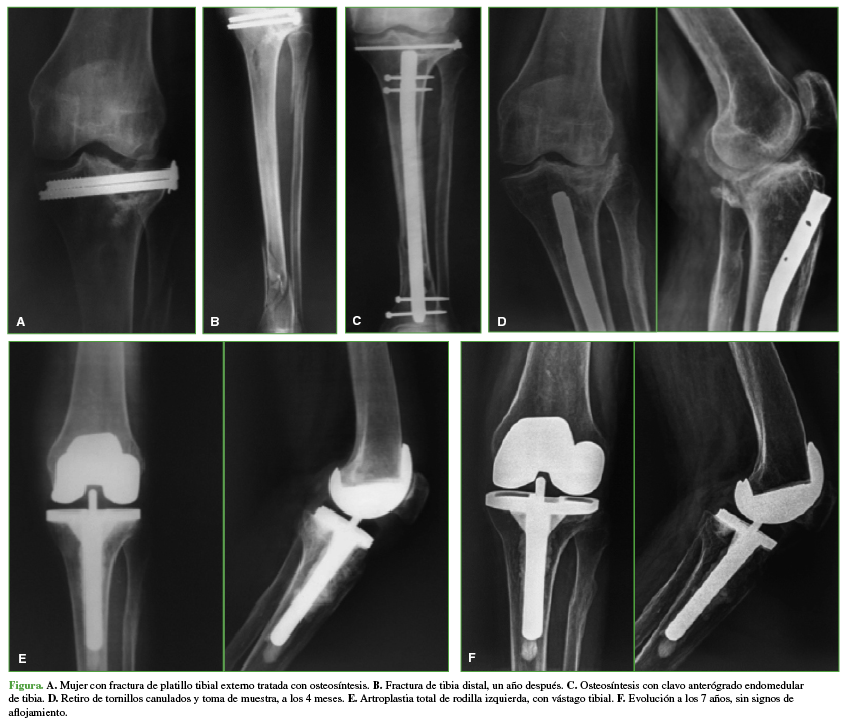

En el análisis radiográfico, se observó la adecuada posición de los componentes protésicos en todos los pacientes (Figura). Se detectaron tres rodillas con evidencia de demarcación tibial, con un seguimiento de 13.2 y 14.5 años, las cuales no eran progresivas durante los controles, y los pacientes no tenían síntomas hasta el final del seguimiento.

A. Mujer con fractura de platillo tibial externo tratada con osteosíntesis. B. Fractura de tibia distal, un año después. C. Osteosíntesis con calvo anterógrado endomedular de tibia. D. Retiro de tornillos canulados y toma de muestra, a los 4 meses. E. Artroplastia total de rodilla izquierda, con vástago tibial. F. Evolución a los 7 años, sin signos de aflojamiento.